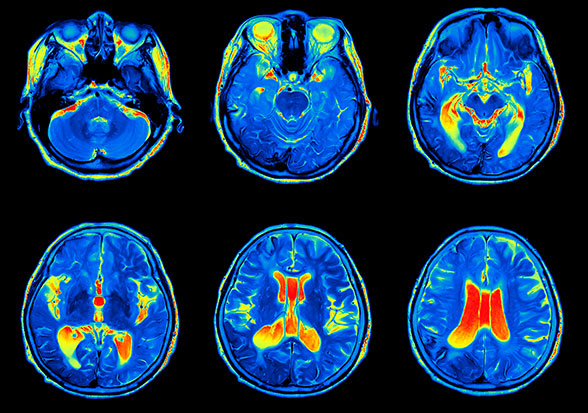

Eficacia y seguridad del zilucoplan en la esclerosis lateral amiotrófica. Ensayo clínico aleatorizado

En este ensayo clínico aleatorizado de zilucoplan en  esclerosis lateral amiotrófica, el tratamiento no alteró la progresión de la enfermedad. El diseño de plataforma adaptativa del ensayo HEALEY ALS Platform permitió probar un nuevo producto en investigación con un uso eficiente del tiempo y los recursos.  JAMA Netw Open 17 de febrero  de 2025

Nuevos desarrollos en miastenia gravis: zilucoplan y rozanolixizumab

Se publican los resultados de sendos ensayos clínicos aleatorizados  de fase 3 de dos nuevos medicamentos para el tratamiento de la miastenia gravis, con mecanismos de acción muy diferentes. Las evidencias son favorables como para ampliar la evaluación a largo plazo. The Lancet Neurology, mayo de 2023.